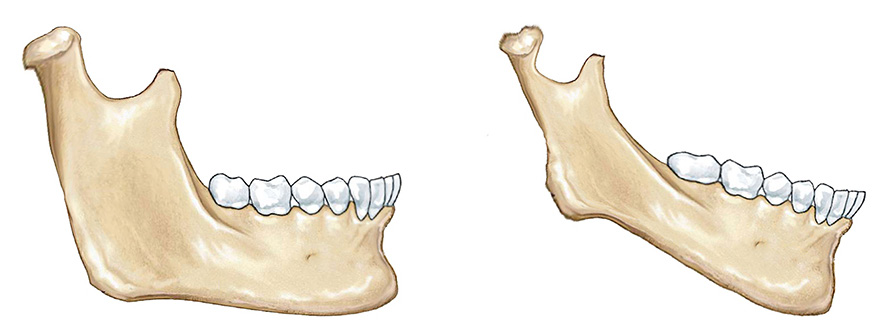

鉴别下颌骨生长发育的潜力要从这几点来看:

(1)髁状突颈部越粗,说明下颌骨发育越好,越细说明下颌骨发育越差。

(2)下颌骨正中联合越厚,说明下颌骨发育越好,越薄说明下颌骨发育越差。

(3)下颌角前切迹越小,说明下颌骨发育越好,越深说明下颌骨发育越差。

(4)下颌升支越宽,说明下颌骨发育越好,越窄说明下颌骨发育越差。

(5)下颌升支长轴倾斜角度越向下,说明下颌骨发育越好,越向前说明下颌骨发育越差。

人类的生长模式是千变万化的,这并不是千真万确的标准,只是我们的临床经验,大概率上预测是合理的。